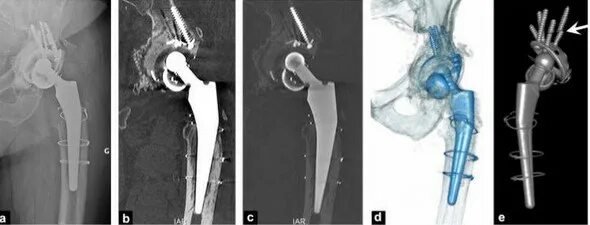

Можно ли эндопротезом делать мрт